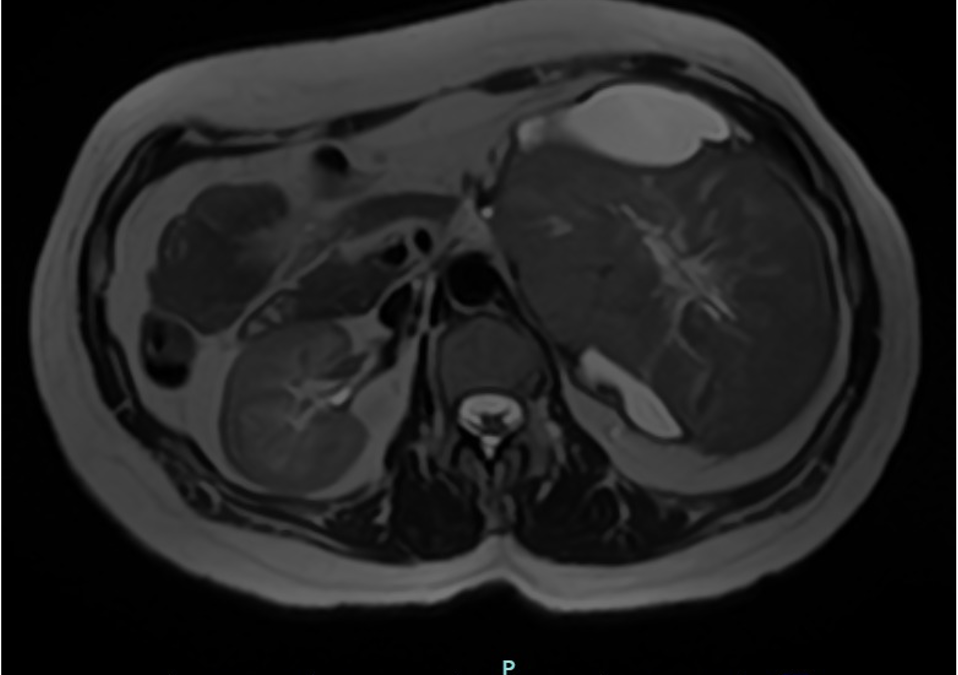

Paciente mujer de 43 años, G0-P000 con antecedentes de hipertensión arterial en tratamiento e historia familiar de cáncer (carcinoma de células de Merkel). Acude por presentar dolor punzante en flanco izquierdo de una semana de evolución. Al examen físico, se palpa masa abdominal móvil y dolorosa. La TC abdominal revela masa sólida ovoidea, de bordes definidos y aspecto encapsulado que mide 139 x 105 mm, asociada a áreas quísticas (Fig 1). Ante estos hallazgos, se realiza nefrectomía radical izquierda. Con la intención de tomar decisiones clínicas inmediatas, se realiza impronta del tumor renal en pieza operatoria observándose células tumorales poligonales con abundante citoplasma eosinofílico granular, membrana citoplasmática bien definida y bordes celulares acentuados. El resultado fue neoplasia de tipo oncocítica que favorece carcinoma cromófobo (Fig 2-5), confirmado histológicamente (Fig 6). Paciente evoluciona favorablemente.